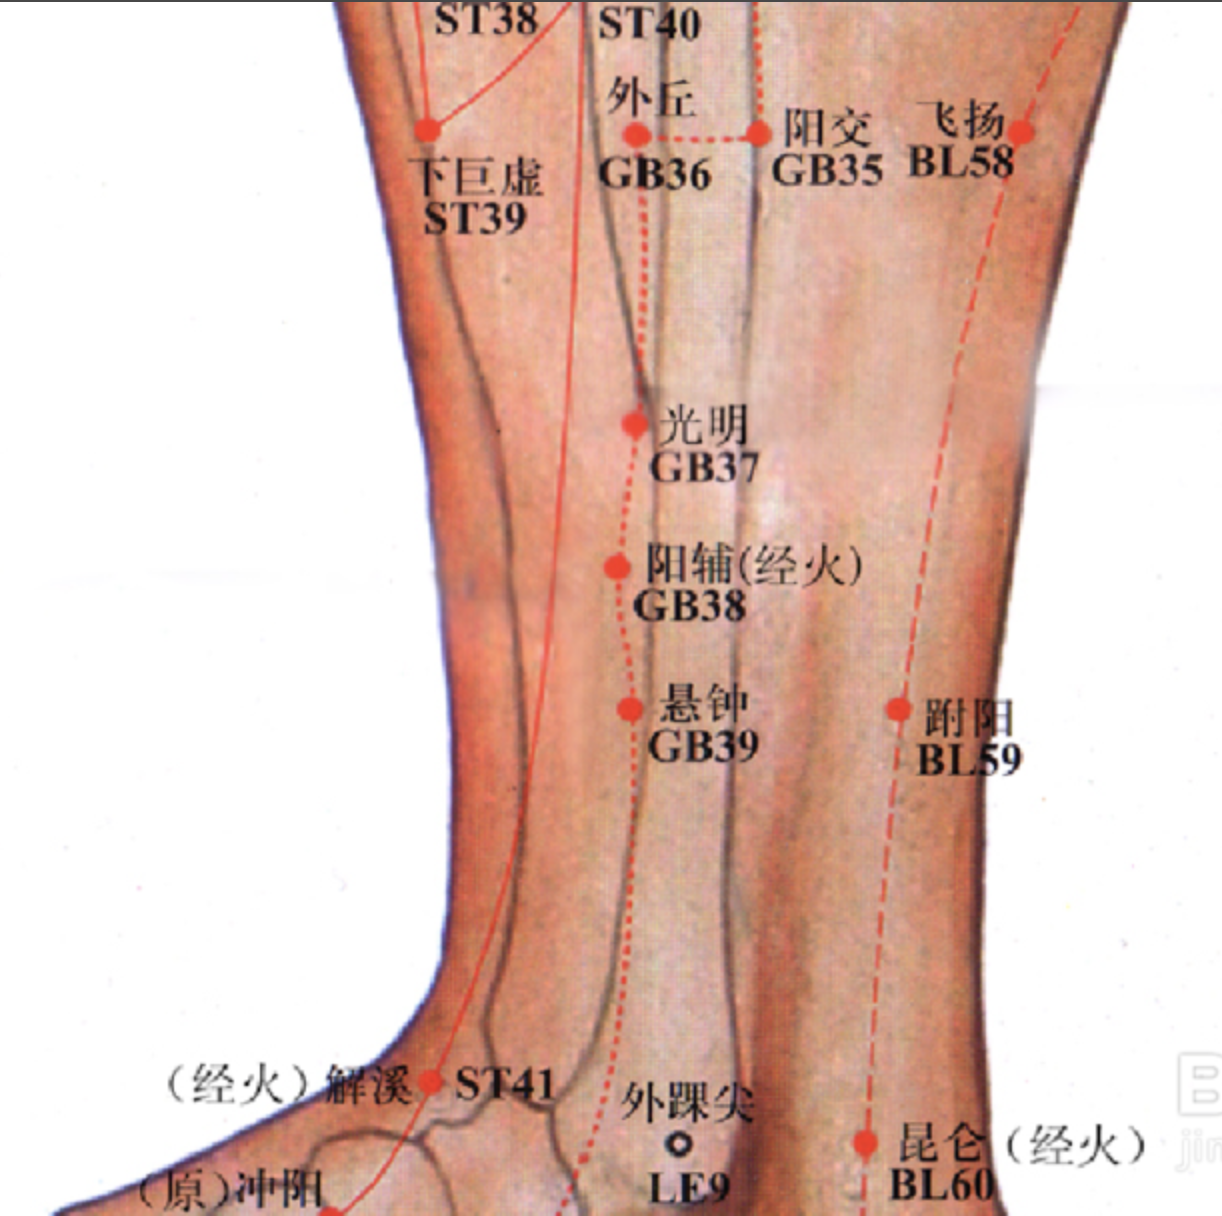

光明

【定位】 在小腿外侧,当外踝尖上 5 寸,腓骨前缘。

【主治】 目痛,夜盲,乳胀痛,膝痛,下肢痿痹,颊肿。

【配伍】 配肝俞、肾俞、风池、目窗、睛明、行间治青光眼和早起白内障。

【刺灸法】 直刺 0.5 ~ 0.8 寸;可灸。

【附注】 胆经络穴。